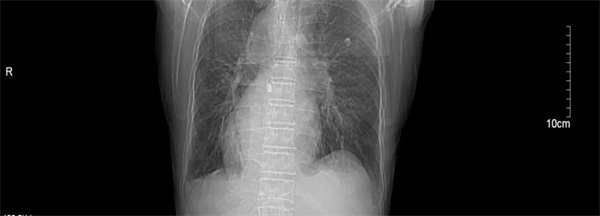

汪大爷因“反复胸闷气喘1周伴头昏”在当地卫生院就诊,心电图检查显示高度-III度房室传导阻滞(心室率40次/分)和镜像右位心心电图。由医共体转诊中心转至我院进一步诊治。入院后,行24小时动态心电图和心脏彩超检查发现,患者不仅患有II度房室传导阻滞,呈2:1下传(最慢心率35次),交界性逸搏伴干扰性房室分离。彩超更是发现汪大爷还是一位罕见的镜面右位心,其心脏及腹腔内脏器官位置与正常人完全相反,如同正常脏器的 “镜中像”,这种先天性畸形的发生几率约为1/100万。